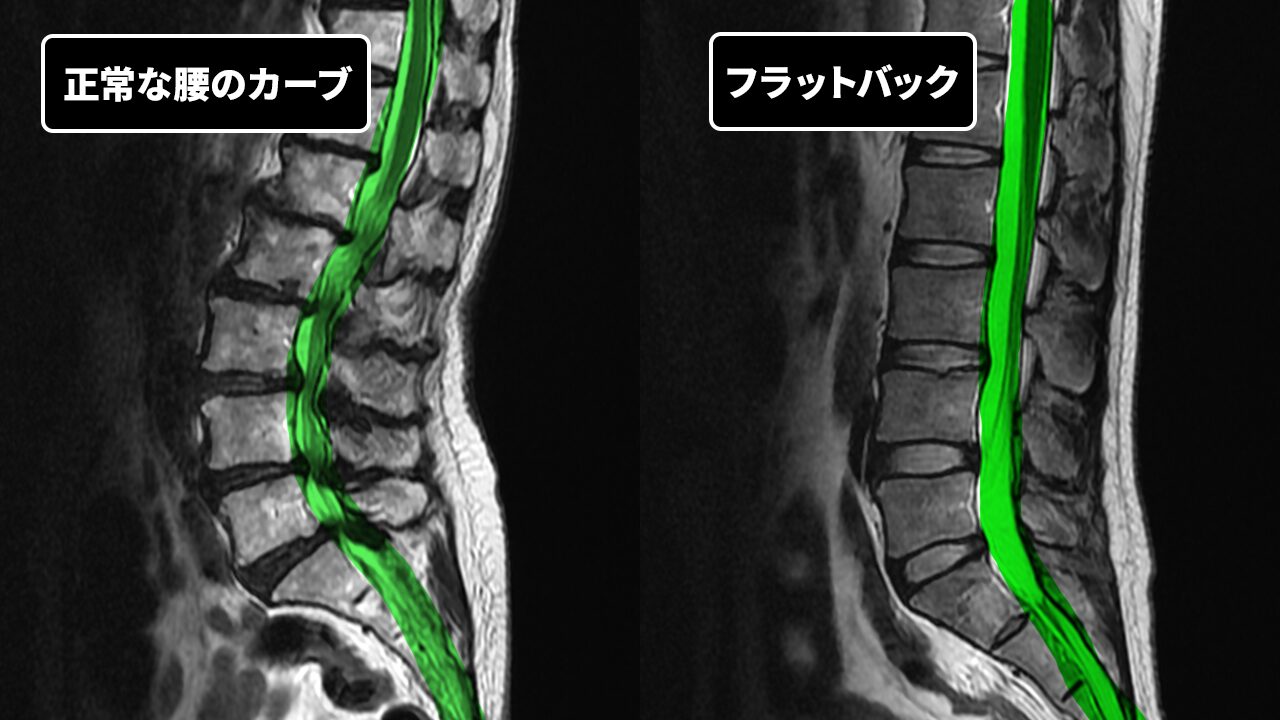

「姿勢がいい=背筋がまっすぐ」と思っていませんか? 実は、人間の背骨は横から見ると緩やかなS字カーブを描いており、腰の部分は自然に前へカーブ(前弯)しているのが正常な状態です。

この自然なカーブが失われて腰が「平ら」になった状態を、医学的には「フラットバック(Flat Back)」と呼びます。もともとは手術の合併症として知られていた病態ですが、近年では手術歴のない若い方にも、生まれつきの体質や生活習慣によってこの状態が存在しうることが分かってきました。

背骨(脊柱)は、首(頸椎)・背中(胸椎)・腰(腰椎)の3つの領域でそれぞれ異なる方向にカーブしており、全体としてS字のバネのような構造をしています。

腰の自然なカーブ(前弯)は、体重を効率よく分散し、衝撃を吸収し、身体の重心を骨盤の上にバランスよく保つ役割を果たしています。正常な前弯角度はおおよそ40〜65度とされています。

このカーブが減ると、上半身の重さが背骨の前方に偏り、クッション役の「椎間板」に過大な負担がかかることになります。これが、フラットバックが問題となる根本的な理由です。

正常な腰とフラットバック